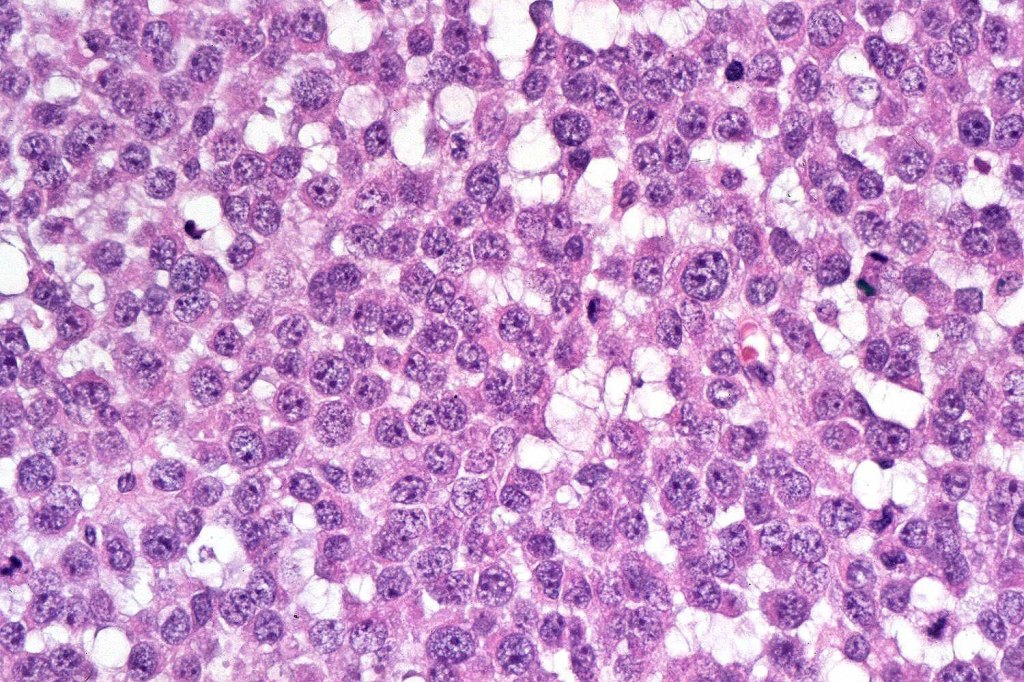

Melanoma with osteoid and chondroid (benign or malignant) are most often encountered in the digits particularly the thumb and large toe, for the other types, they are too rare to make any meaningful clinical comments. Documented heterologous elements include: